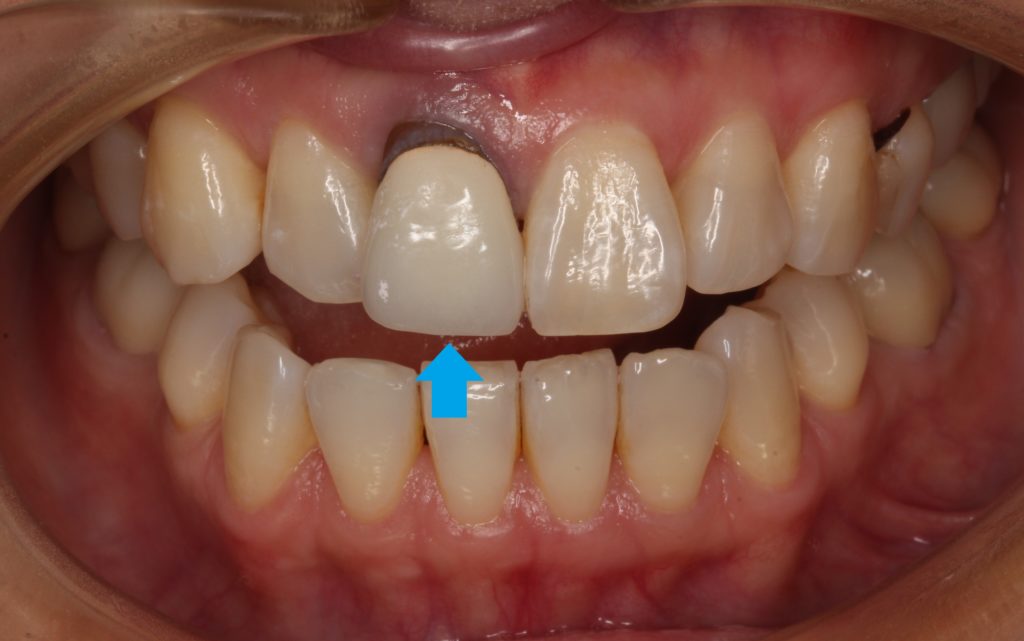

40代女性。「差し歯の入っている歯の根元が黒く、綺麗に治したい」という希望の方です。

矢印の歯ですが、根元が黒いのがすぐに分かります。

こちらの歯は若い頃に差し歯になってしまったようで。年々、根元のが目立ってきたようです。